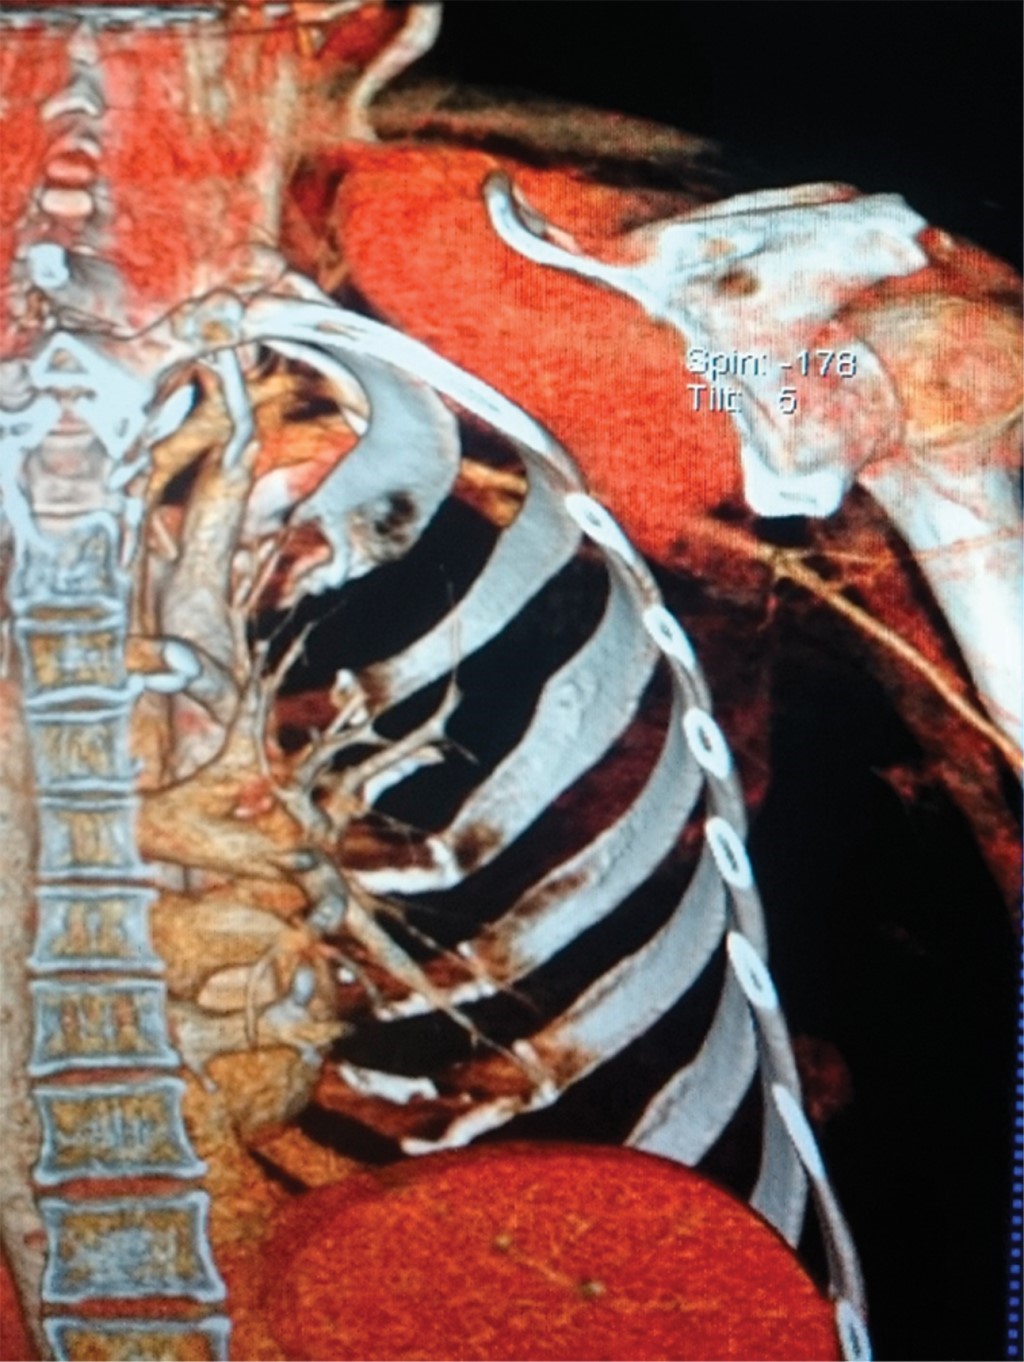

Due to postoperative pain, the patient was sent to radiotherapy, after an MRI that showed a subscapular lesion with extension towards the supraclavicular fossa, involving the subscapularis muscles. It could not be established with certainty if it was a fatty tumor, nor if it had an intrathoracic extension; therefore, a CT scan was performed showing a heterogeneous right subscapular tumor measuring 11.6 × 11.5 × 9.4 cm, with increased vascularity, that was compressing and displacing the internal jugular vein. It was not eroding the ribs, but it was eroding the scapular spine. No adenopathy was seen. The tumor was shown to involve the subscapularis muscle and replacing it in its entirety (Figures 1 and 2). The axillary and supraclavicular neurovascular bundles were identified. In May 2055 a percutaneous biopsy was performed with a histology report of myofibromatosis.